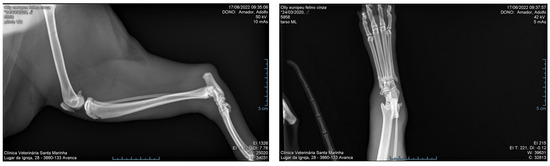

On physical examination, the temperature was 41.7 °C and the right hind limb was edematous, especially in the tarsal area, painful to the touch, and without support. The animal was hospitalized and treated with IV fluids, and antibiotic therapy (enrofloxacin and amoxicillin + clavulanic acid) was started. Twelve hours after admission, it presented a generalized tonic–clonic seizure treated with IV diazepam. Radiography of the limb was performed (Figure 2) and blood was taken for analysis, where leukopenia with neutropenia and increased ALT, creatinine, and urea were observed (Table 1).

Figure 2. Radiography of the right hind limb of a male cat 12 h after a snakebite.